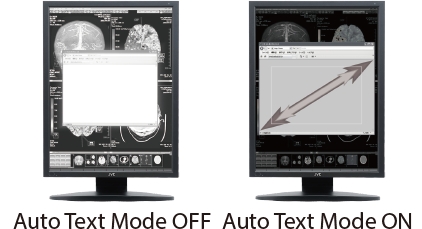

Tryb Tekstowy --- Automatyczne zmniejszanie jasności podświetlenia w obszarach tekstowych. (ang.: Auto Text Mode)

Automatyczna kontrola jasności obszarów tekstowych, mająca na celu zmniejszenie zmęczenia oczu przy pracy z worklistą lub pisaniu tekstów.